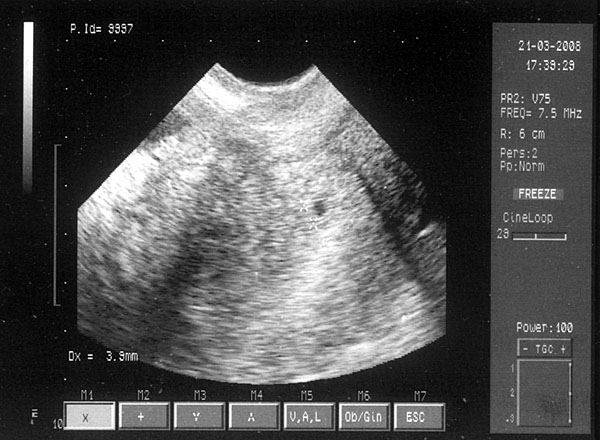

csak gyorshR mert anyóséknál vagyunk vendégségben...van egy szép szabályos 3,9 mmes petezsákocska :lol: :lol: abzsolut jó helyen és éljen!!!!!!

itt a kis sztárfotnk picikénkről